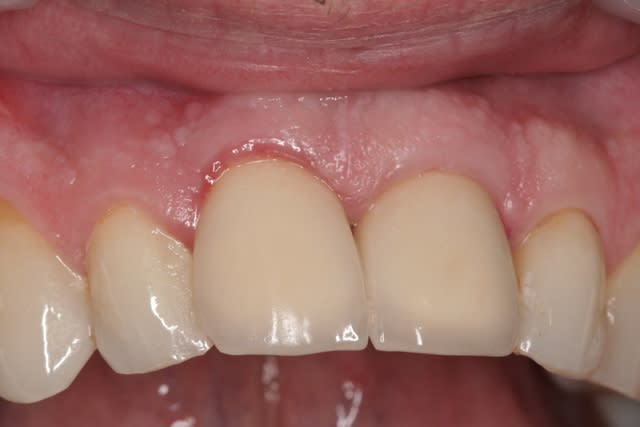

pluton

22/10/2011 à 11h59

le hasard fait parfois bien les choses...patient revu ce matin pour une "bricole" sur une restauration postérieure...

il est intéressant de voir la maturation des tissus mous...et en plus VS des différences au niveau de l'hygiène, pas mal secteur 2 mais perfectible secteur 1...

ici on est à 3 mois post pose prothèses d'usage...la photo, prise un peu décalée, donne l'impression d'une différence de hauteur des collets, mais il n'en est rien (ou alors très peu...)

quand même content du résultat...;-) même si j'ai (lourdement)insisté pour que l'hygiène soit un peu mieux suivie...